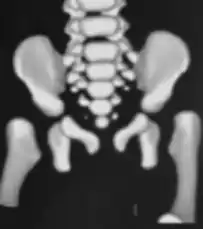

CT hips

X-ray- dislocation of hips